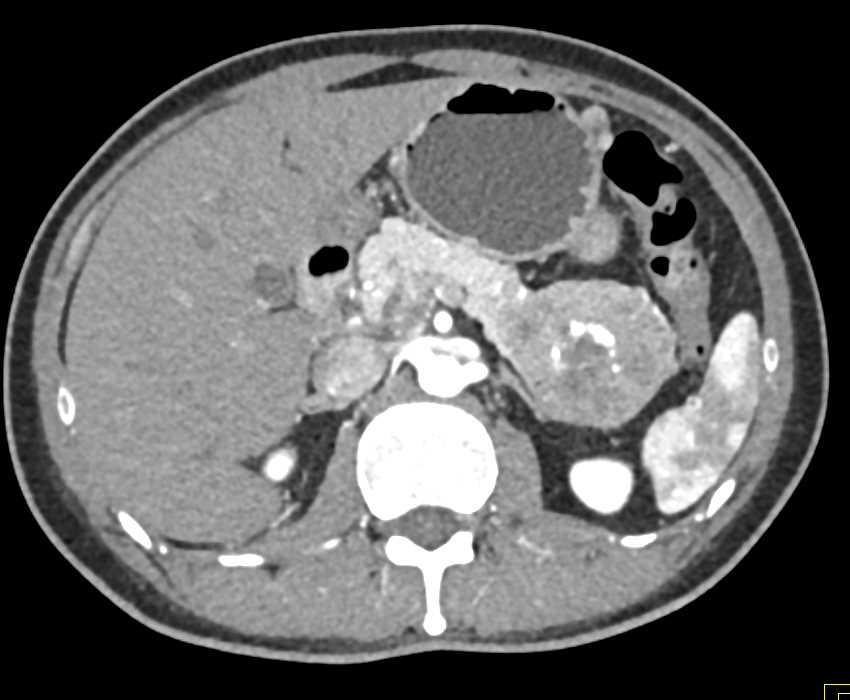

PNET Tail of the Pancreas